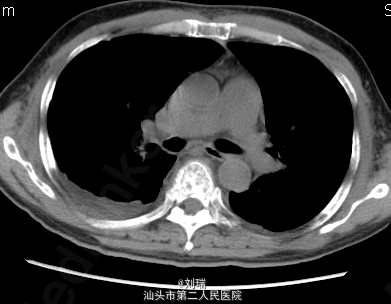

经上述处理,患者症状稍好转后行胸CT增强:双肺上叶继发型肺结核,双肺散在感染性病变;心包少量积液;双侧少量胸腔积液。经感染科会诊:考虑结核急性发作期可能性不大。继续上述对症处理后,患者症状逐渐好转;应用万珂后骨痛症状较入院时好转。 讨论:因万珂所致急性肺损伤发生率极低;最终考虑该患者为哮喘发作;化疗后出现气促、呼吸困难是否与万珂相关?